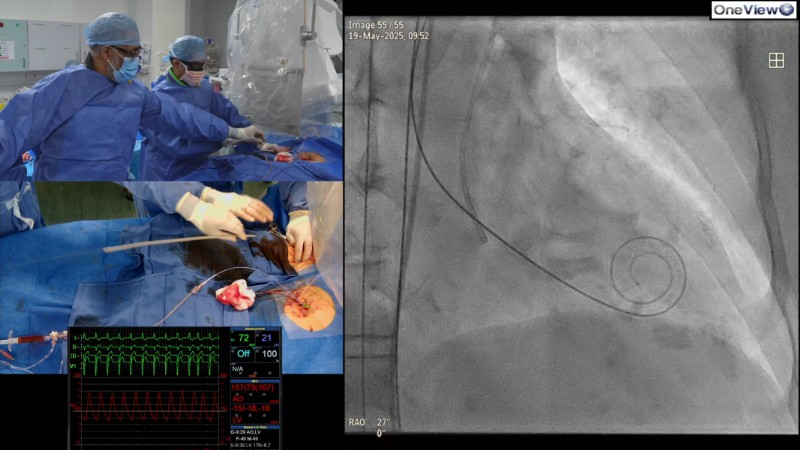

Optimising patient outcomes in self-expandable TAVI starts with a clear plan for today, and tomorrow. This EuroPCR 2025 session explores how to make each step count, from access to implantation and closure, using a real-life case of a 77-year-old woman with severe symptomatic aortic stenosis and multiple comorbidities.